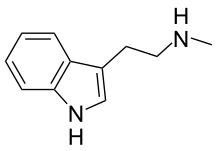

| NMT | Plants | H | H | CH3 | N-methyltryptamine | 61-49-4 |